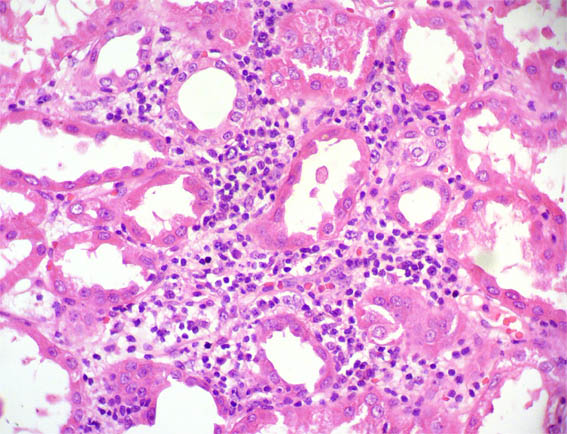

Figure 3. H&E, X200.